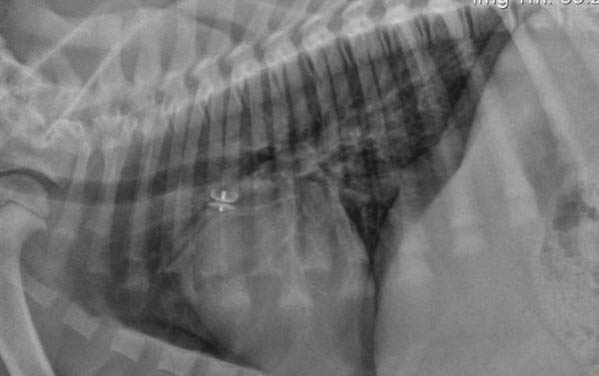

桃子適口性極佳,因此許多狗狗吃桃子時都會“狼吞虎咽”,并不顧及其中的桃坑。一旦狗狗不慎將桃坑一并吞下,很可能會因卡住喉嚨而窒息或腸道異物梗阻。同時,堅硬的桃坑也會損壞它們的牙齒或下顎。